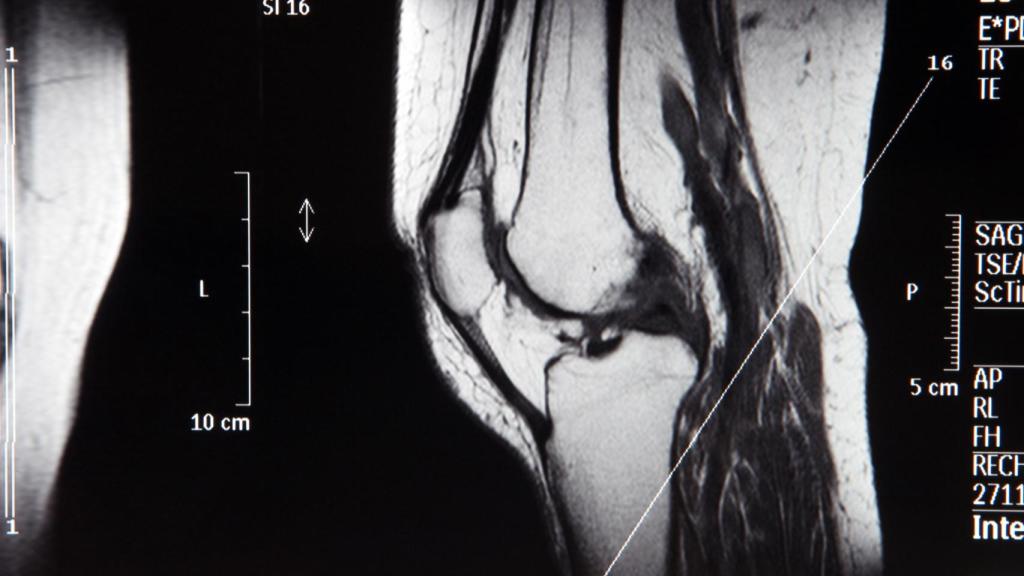

Una prueba de imagen de la rodilla.

Una prueba de imagen de la rodilla. iStock